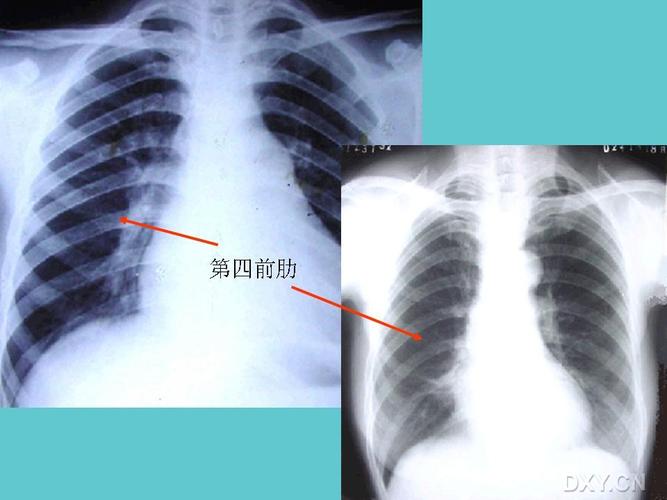

秒懂胸片!扒一扒胸片的基础知识

【请教】少量,中量,大量胸腔积液的划分标准是什么?

秒懂胸片扒一扒胸片的基础知识

正常胸片图片图解

正常胸片和异常胸片

正常胸片和肺炎胸片图

正常胸片影像图片

正常胸片

胸片怎么看